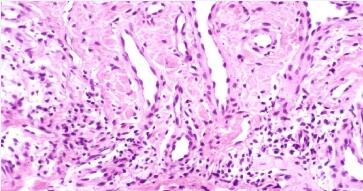

突然出现的风团样丘疹,呈圆形或纺锤形,黄豆至蚕豆大小,伴有轻度水肿,淡红或鲜艳。

炎症明显时中心有水疱,甚至形成张力性大疱,自觉剧痒。皮损多发于四肢、躯干,呈散在或群集分布,有时可见3—4个丘疹呈线状排列。

皮损可分批出现,新旧交替或重叠。本病有自限性,每批皮损约经3—7天,皮损消退后遗留色素沉着。